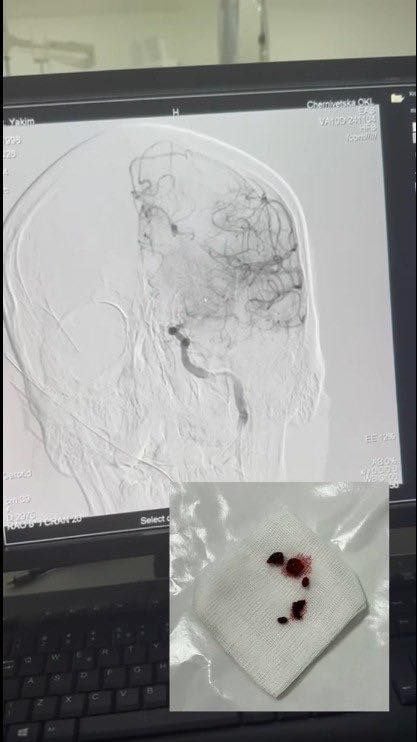

30-річний чоловік потрапив в лікарню через виклик швидкої допомоги. У нього раптово порушилося мовлення, свідомість, зникли відчуття у правих кінцівках. У відділенні невідкладних станів пацієнта оглянув невролог. Під час комп’ютерної томографії головного мозку лікарі виявили велику кількість тромбів у великій судині – лівій внутрішній сонній артерії. Пацієнту терміново провели тромболітичну терапію та ендоваскулярне втручання.

«Під час процедури судину відкрили, забрали тромби, кровопостачання головного мозку відновили. Уже наступного дня пацієнт мав позитивну динаміку, рухи у кінцівках відновилися. Зберігається моторна афазія, з якою він працює разом із логопедом. Прогноз – сприятливий», – зазначила лікарка-неврологиня інсультного відділення Ірина Житарюк.

Лікарі видалили тромби з судини